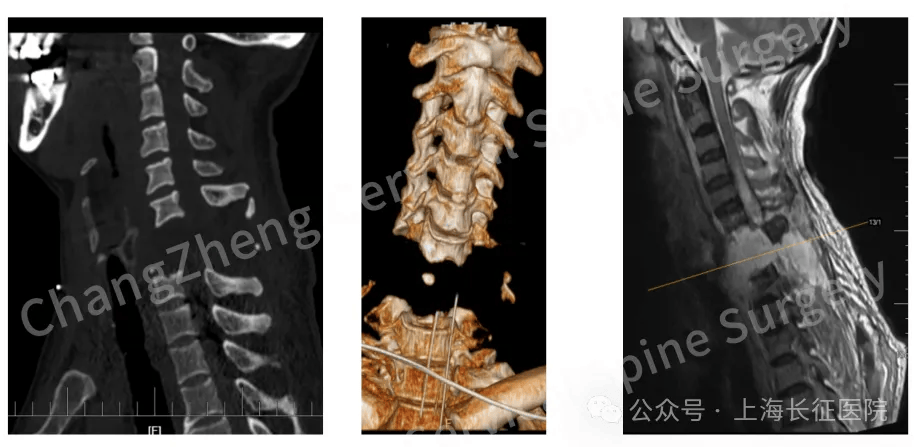

从业近30年,上海长征医院颈椎外科病区主任陈华江教授接诊过无数凶险的颈椎外伤患者,但称得上是“身首离断”的,他还是第一次遇到。 眼前这位患者,几乎已被宣判“死刑”。影像学检查显示,患者发生了罕见的大跨